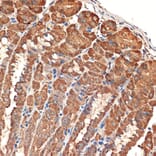

Immunohistochemistry analysis of paraffin-embedded human colon carcinoma tissue using Anti-Bcl G/BCL2L14 Antibody [ARC2474] (A307106) at a dilution of 1:100 (40x lens). Perform microwave antigen retrieval with 10 mM Tris/EDTA buffer pH 9.0 before commencing with IHC staining protocol.